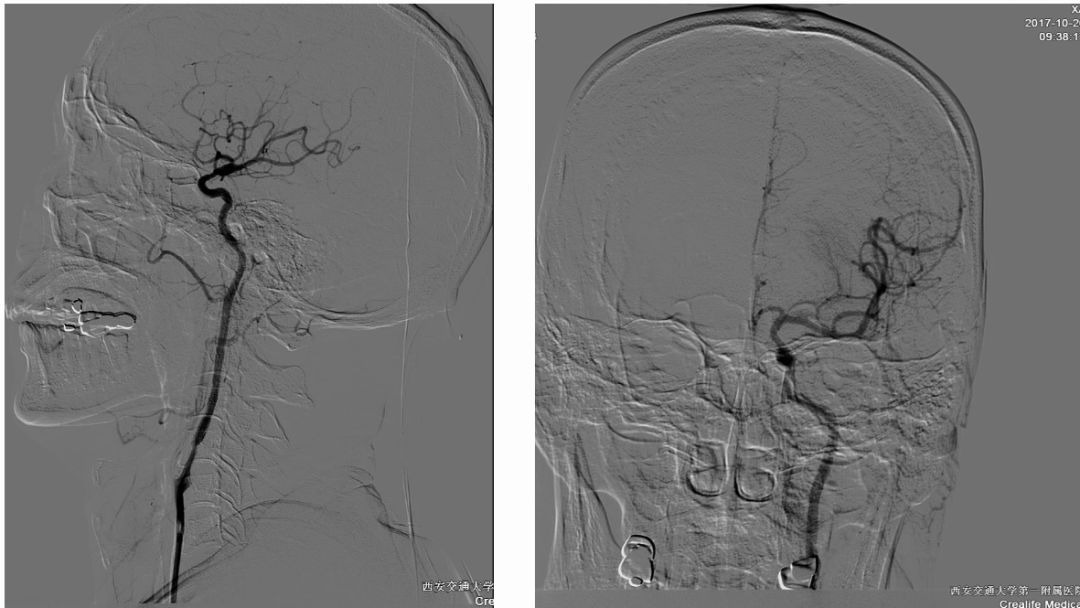

术后正侧位造影图片

术后即刻CT

术后24h CT

术前造影:

串联病变

双颈动脉支架

术后CT